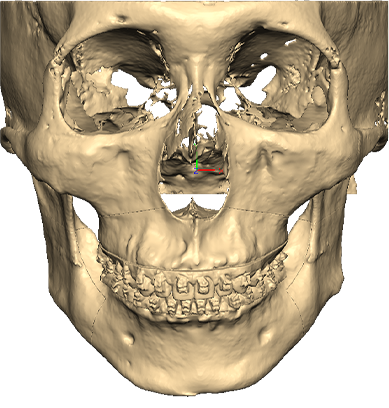

STEP 01

Cutting guide를 이용하여 3D로 계획된 삭제량만큼 뼈를 삭제

STEP 02

Wafer를 이용해 상악의 돌출을 뒤로 교정 무턱의 하악을 앞으로 빼내어 정상교합에 위치시킨 뒤, 맞춤형 Plate로 뼈를 고정

수술결과

무턱 개선 : 턱 끝 기준 17mm 전진